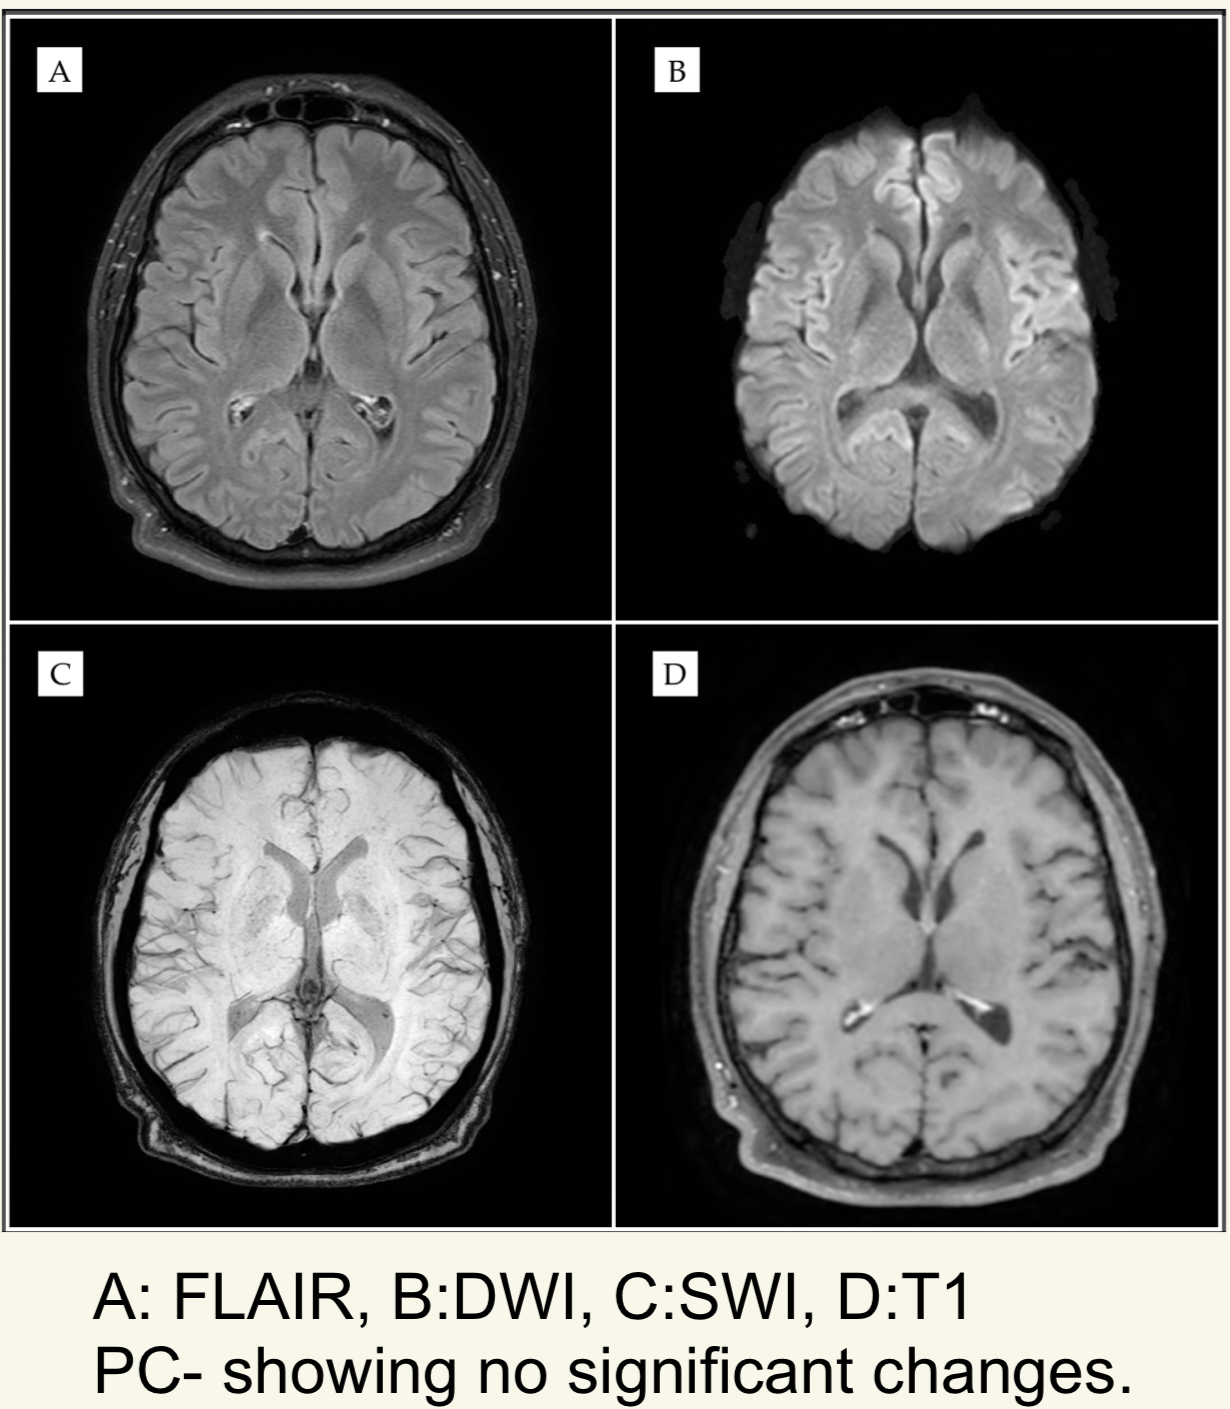

Neuroimaging & CSF: MRI revealed mild cerebral and cerebellar atrophy without midbrain or basal ganglia involvement; CSF showed elevated protein (70 mg/dL) with mild pleocytosis (3 WBCs).

MRI sequences